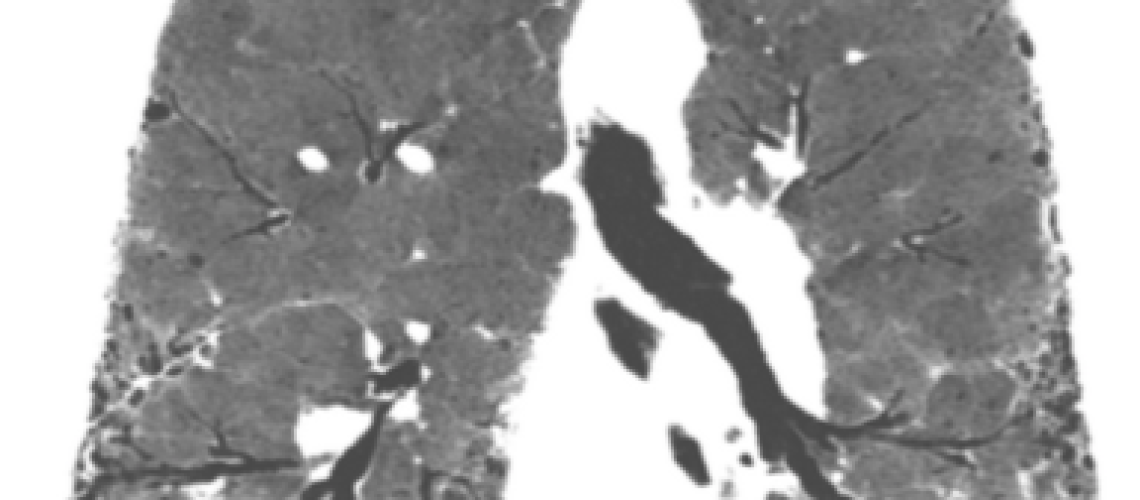

La fibrosis pulmonar idiopática es la enfermedad pulmonar intersticial mas frecuente y no se conoce la causa que la provoca. Origina un endurecimiento o cicatrización progresiva (fibrosis) del tejido pulmonar que hace que el paciente presente fatiga con los esfuerzos y a veces tos irritativa con lo que el paciente pierde de forma acelerada capacidad pulmonar. Suele aparecer a partir de los 50 años y es mas frecuente en el hombre que en la mujer. En ocasiones hay antecedentes de familiares afectos de fibrosis pulmonar. Para el diagnóstico es fundamental en TAC de alta resolución torácico y en algunos pacientes la biopsia pulmonar. Es una enfermedad con mal pronóstico y sin tratamiento el 50% de los pacientes fallece a los 3-5 años del diagnóstico. En la actualidad existen fármacos antifibróticos que ayudan a controlar la enfermedad.